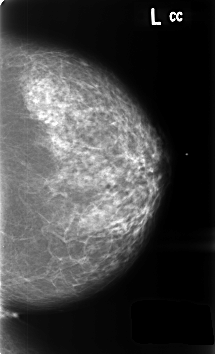

B_3459_1.LEFT_CC

LEFT_CC LINES 4592 PIXELS_PER_LINE 2784 BITS_PER_PIXEL 12 RESOLUTION 50 NON_OVERLAY

LEFT_MLO LINES 4640 PIXELS_PER_LINE 2872 BITS_PER_PIXEL 12 RESOLUTION 50 NON_OVERLAY